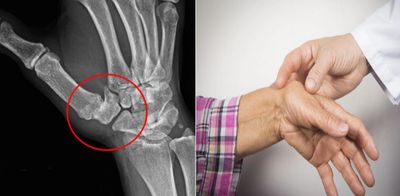

Cuando hablamos de fracturas de muñeca, por lo general, nos estamos refiriendo a fracturas del extremo distal del radio. Sin embargo la muñeca como articulación, implica otros huesos como el cúbito y los huesos del carpo. Dejando esto en claro, vamos a hablar breve y específicamente de las fracturas del extremo distal del radio.

Este tipo de fracturas puede presentarse de manera extraarticular o intraarticular (como es el caso de la foto), dependiendo de si el trazo de fractura invade o no la articulación radiocarpiana. Dependiendo del tiempo de evolución, del trazo de fractura y del segmento del hueso en que se presente, se toman las decisiones acerca de la conducta a seguir. Esto puede ir desde la "simple" inmovilización hasta la resolución quirúrgica de la fractura, en la que utilizamos clavos, tornillos y/o placas según lo conveniente para cada caso. Hoy en día, utilizamos una herramienta, a mi parecer fundamental para la resolución de estos casos, que es el uso del artroscopio. Este equipo, nos permite introducir una minicamara en la articulación para ayudarnos a que la reducción de la fractura sea lo mas precisa posible y a la vez, nos permite reparar cualquier daño asociado que pueda haber dentro de la articulación (lesiones ligamentarias, fibrocartilago triangular, etc.).